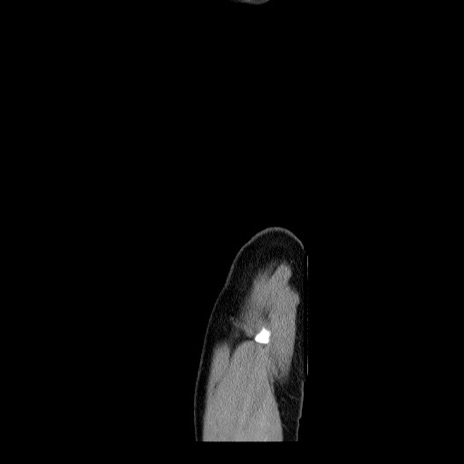

症例34(矢状断像)

【症例】60歳代 男性

【主訴】右鼠径部膨隆

【現病歴】1年程前より右鼠径部膨隆あり。自己にて還納可能だったため放置していた。3時間前より右鼠径部の脱出を認め、還納困難となり受診。

【身体所見】右鼠径部に小児頭大の膨隆あり。弾性硬であり、用手還納は困難。左鼠径部にも膨隆を認める。脱出はなし。